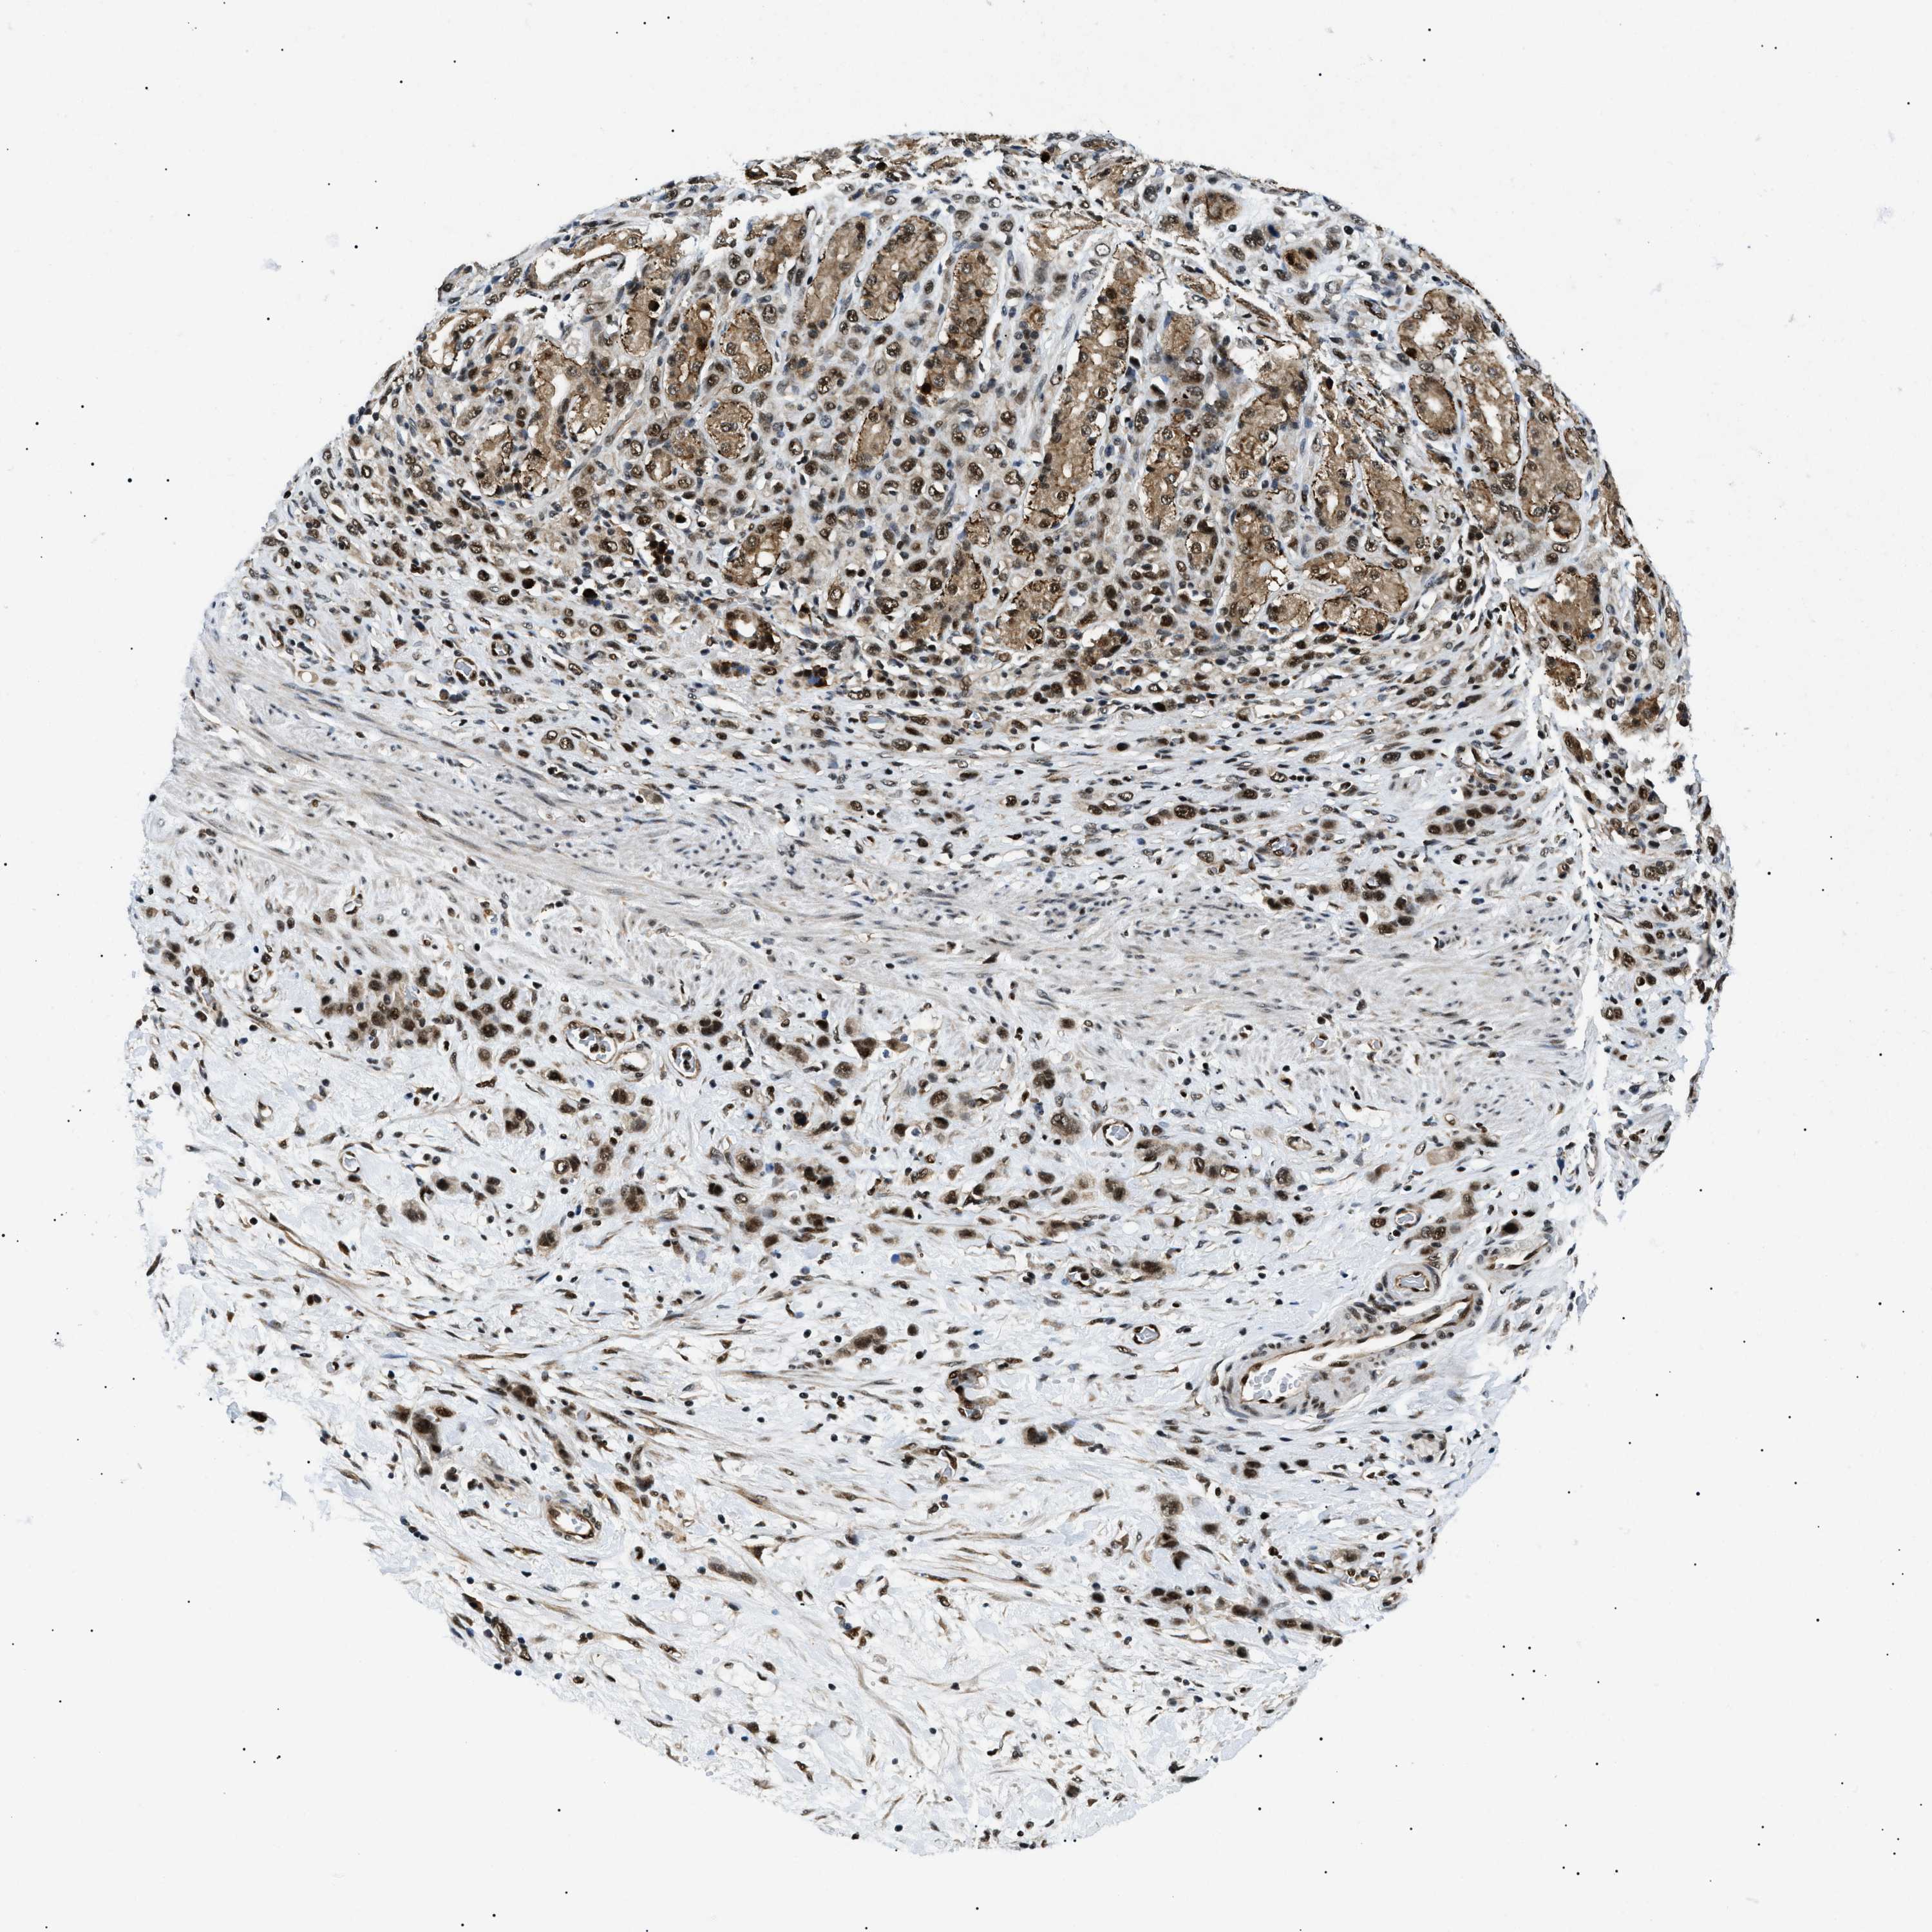

STOMACH CANCER - Protein expressioni

A mouse-over function shows sample information and annotation data. Click on an image to view it in a full screen mode. Samples can be filtered based on level of antibody staining by selecting one or several of the following categories: high, medium, low and not detected. The assay and annotation is described here.

Note that samples used for immunohistochemistry by the Human Protein Atlas do not correspond to samples in the TCGA dataset.

Antibody stainingi

Antibody staining in the annotated cell types in the current human tissue is reported as not detected, low, medium, or high, based on conventional immunohistochemistry profiling in selected tissues. This score is based on the combination of the staining intensity and fraction of stained cells.

Each image is clickable and will lead to virtual microscopy that enables deeper exploration of all samples and also displays staining intensity scores, fraction scores and subcellular localization as well as patient and tissue information for each sample.

Antibody HPA062997

Antibody CAB014874

Staining

High

Medium

Low

Not detected

Intensity

Strong

Moderate

Weak

Negative

Quantity

>75%

75%-25%

<25%

None

Location

Nuclear

Cytoplasmic/membranous

Cytoplasmic/membranous,nuclear

Adenocarcinoma, NOS

Adenocarcinoma, High grade